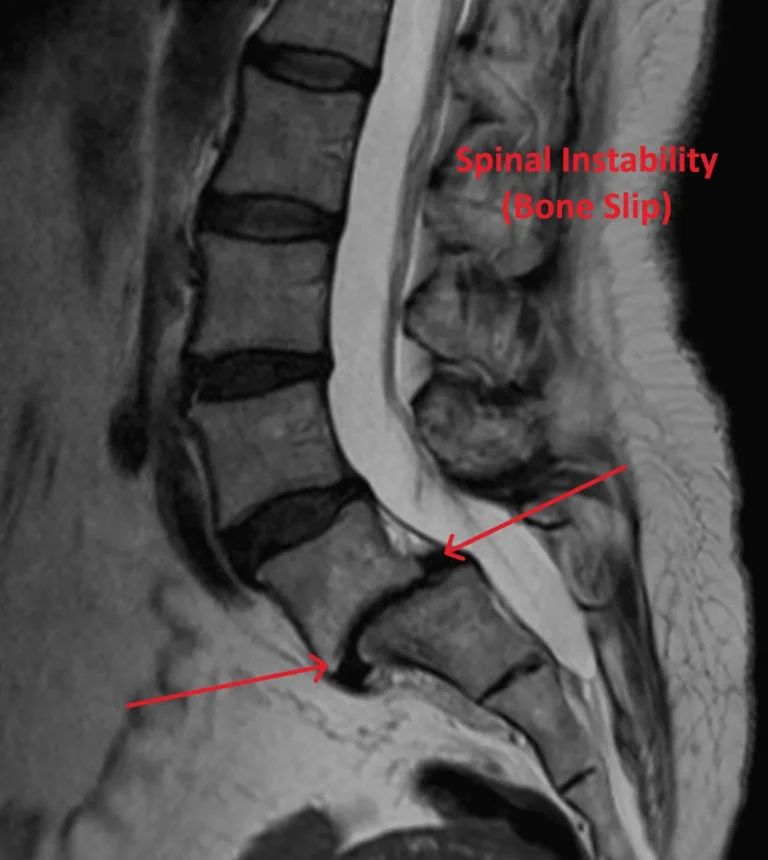

Spinal Instability

MRI of lumbar spine showing recurrent disc herniation post discectomy highlighted by arrows.

Recurrent Herniation